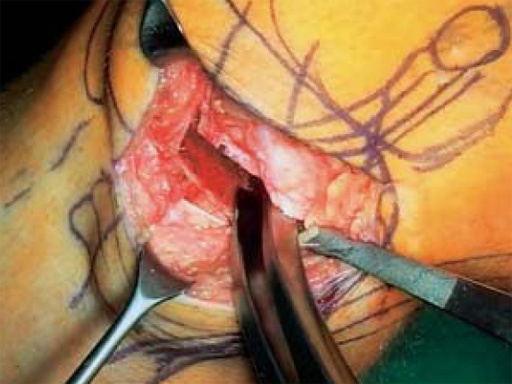

The correction is planned on a long-leg standing x-ray. After surgery, the mechanical axis should pass through a point 63% on the lateral side of the total width of the tibial plateau in the frontal plane. A transverse or slightly oblique incision is used to avoid damage to the saphenous nerve. The distal fibers of the medial collateral ligament are detached from the tibia. Under fluoroscopic control, two wires are placed in the proximal tibia marking the transverse osteotomy plane. The cut usually starts at the upper margin of the pes anserinus and ends at the tip of the fibula on the lateral side. The wires are placed exactly parallel to the tibial plateau thus taking into consideration the individual tibial slope of the patient. An incomplete cut of the posterior two-thirds of the proximal tibia is performed with an oscillating saw guided by the wires. Continuous irrigation avoids burn injury to the bone. A second osteotomy is now performed in the anterior third of the tibia in an angle of 100 ending above the patellar tendon insertion. A smaller saw blade is used and the complete anterior cortex is cut exactly in the frontal plane. The osteotomy is now gradually opened by inserting flat chisels or a spreader-chisel into the posterior osteotomy cleft. This process may take some minutes and can usually be completed without fracture of the lateral cortex. A bone spreader is now placed in the posteromedial edge of the tibia and the chisels are removed. The leg is extended and the correction is checked with the fluoroscope. A long metal rod is placed between center of the hip joint and center of the ankle joint. The projection of this rod should be at the planned point of correction on the tibial plateau lateral of the midline. Eccentric collapse of the medial joint space may cause accidental overcorrection. In this case pressure on the foot may simulate loading and body weight. The correction can be fine-tuned by opening or closing the spreader. The TomoFix Medial Tibia Plate is now placed in a subcutaneous pocket. The implant is precontoured and usually fits well to the bone surface. The distance holders avoid compression of the medial collateral ligament and the pes anserinus. Three proximal bolts are placed near the subchondral sclerosis zone. The position of the bolts is adapted to the anatomy of the proximal tibia giving optimum purchase for the bolts. An oblique lag screw is inserted distal to the osteotomy. This screw in the first combination hole allows careful compression of the lateral osteotomy hinge and pretensioning of the implant. A stab incision is created on the shaft and the implant is fixed monocortically with bolts. The lag screw and the distance holders are replaced by bolts. The medial collateral ligament is released longitudinally to reduce medial compartment pressure and the wound is closed in layers. An overflow drain may be used. Clinical and experimental work has proven that when this technique is closely followed, corrections up to and over 15 mm can be performed without bone grafting or use of bone substitutes.